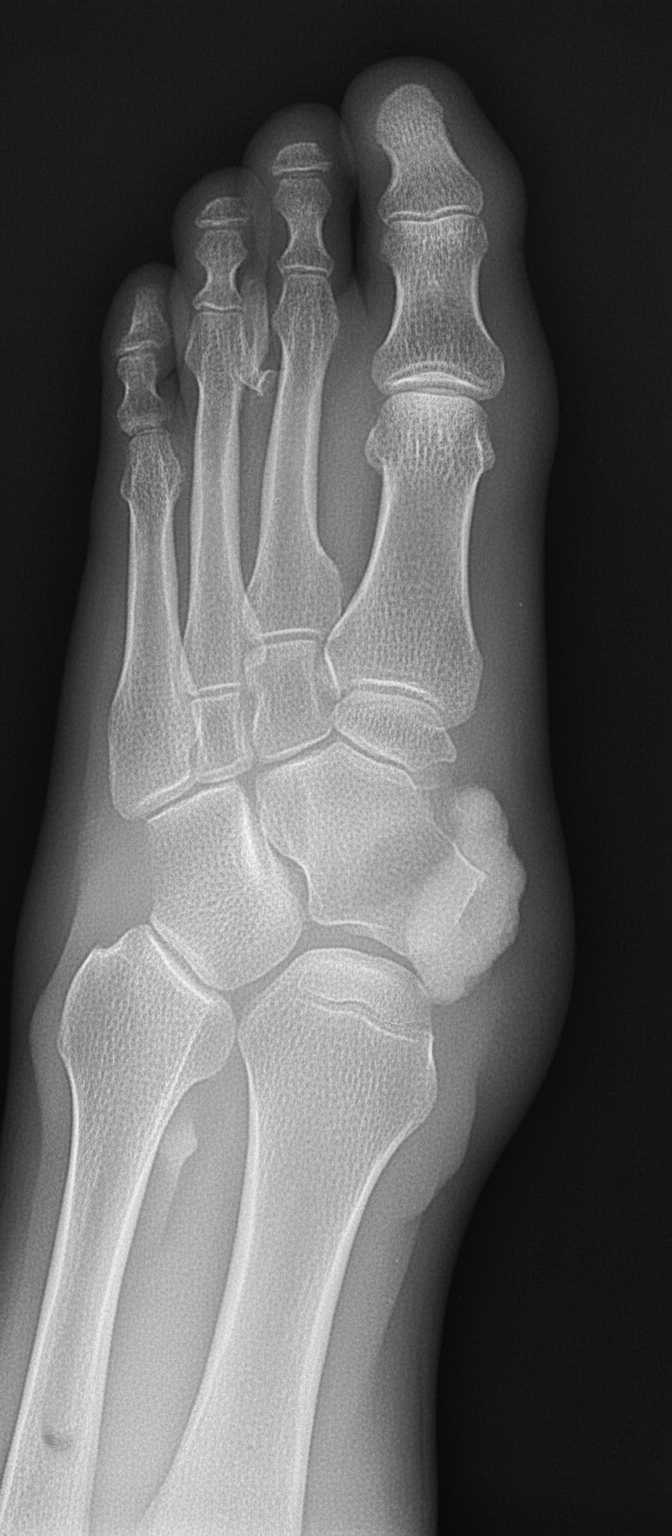

Which disease is shown by the following X-ray of a foot?

Explanation: ***Gout*** - Classic X-ray features include **punched-out erosions** with **overhanging edges** (Martel sign) and **soft tissue tophi**, typically affecting the first metatarsophalangeal joint. - **Preserved joint space** and absence of **periarticular osteoporosis** are characteristic findings that distinguish it from other arthropathies. *Rheumatoid arthritis* - Shows **symmetric joint erosions** with **periarticular osteoporosis** and **joint space narrowing**, unlike the preserved joint spaces in gout. - Typically affects **metacarpophalangeal** and **proximal interphalangeal joints** with **swan neck** or **boutonniere deformities**. *Osteoarthritis* - Characterized by **joint space narrowing**, **osteophyte formation**, and **subchondral sclerosis** rather than punched-out erosions. - Commonly affects **weight-bearing joints** like knees and hips, with **Heberden's** and **Bouchard's nodes** in hands. *Psoriatic arthritis* - Shows **pencil-in-cup deformity** and **ankylosis** with **asymmetric joint involvement**, different from gout's punched-out pattern. - Associated with **psoriatic skin lesions** and **nail pitting**, often affecting **distal interphalangeal joints**.

Explanation: **Explanation:** **Windswept deformity of the foot** is a classic clinical feature of **Rheumatoid Arthritis (RA)**. It describes a specific combination of forefoot deformities where the toes appear "blown" to one side. This occurs due to a combination of **hallux valgus** (great toe deviating laterally) and **fibular (lateral) deviation** of the lesser toes at the metatarsophalangeal (MTP) joints. The underlying pathology involves chronic synovitis leading to the destruction of collateral ligaments and joint capsules, causing the toes to drift laterally. **Analysis of Incorrect Options:** * **Rickets (Option A):** While Rickets is famous for "Windswept deformity," it occurs at the **knees** (one knee in genu valgum and the other in genu varum), not the foot. This is a common "trap" in exams. * **Hyperparathyroidism (Option C):** This condition typically presents with subperiosteal bone resorption (classically in the phalanges), Brown tumors, and "Salt and Pepper" skull, but not specific windswept foot deformities. * **Scurvy (Option D):** Vitamin C deficiency presents with subperiosteal hemorrhages, Scorbutic rosary, and radiographic signs like Wimberger’s ring sign and Frankel’s line, rather than joint deviations. **High-Yield Clinical Pearls for NEET-PG:** * **Windswept Knee:** Rickets (most common), Osteomalacia, or Skeletal Dysplasias. * **Windswept Foot:** Rheumatoid Arthritis. * **Rheumatoid Foot Triad:** Hallux valgus, Fibular deviation of toes, and Subluxation of MTP joints (leading to "daylight sign"). * **Hand Deformities in RA:** Swan neck deformity, Boutonniere deformity, and Ulnar deviation at MCP joints.